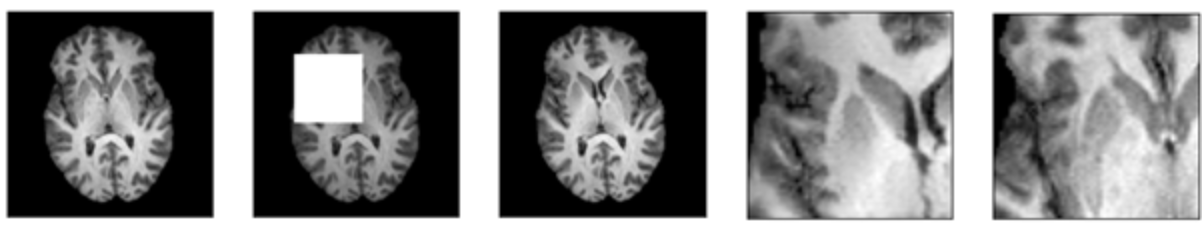

As shown in figure 2, one can see how the problem definition changed according to the amount of data masked. For smaller window sizes, the inpainting network is only required to reconstruct a handful of pixels. However, with larger masks the network is required to reconstruct texture and structure. Additionally, due to adversarial training, the network produces reconstructions without blur.